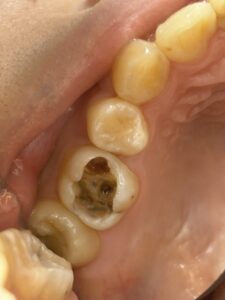

虫歯で奥歯が欠けてズキズキ痛い、噛めない 咬みにくい 食事もだんだんしづらく ついでに歯が冷たい水にしみる!

歯の神経を取る根の治療 根管治療をすれば治ります。治した後は 保険適応でハイブリッドセラミックやCAD/CAM冠インレー クラウンなどで白い歯で治すといいですね。もちろんセラミックやジルコニアの治療もあります。